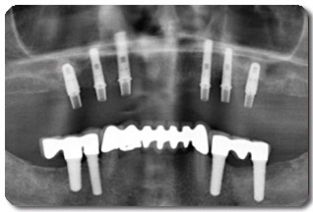

Röntgenopnames spelen een belangrijke rol bij de planning van de ingreep. Op een panorama röntgenfoto (OPG) kan de implantoloog goed de afstand tot anatomische structuren zoals een belangrijke zenuw in de onderkaak of de kaakbijholte in de bovenkaak, inschatten. In moeilijkere gevallen kunnen er meer opnames worden gemaakt zoals een CT-scan, waarbij het zelfs mogelijk is met behulp van de computer de positie van de implantaten driedimensionaal te plannen.

De breedte van de kaakwal is op de normale (twee-dimensionale) röntgenfoto's niet goed in te schatten, hiervoor zullen soms de eerder genoemde driedimensionale opnames gemaakt moeten worden (tomogram/CT-scan). Gelukkig kan de implantoloog door de kaakwal in de mond te onderzoeken vaak ook voldoende informatie verkrijgen. In sommige gevallen kan met een naaldje tot aan de benige kaakwal geprikt worden om de breedte van het bot onder het tandvlees te beoordelen, dit wordt ridge-mapping genoemd.